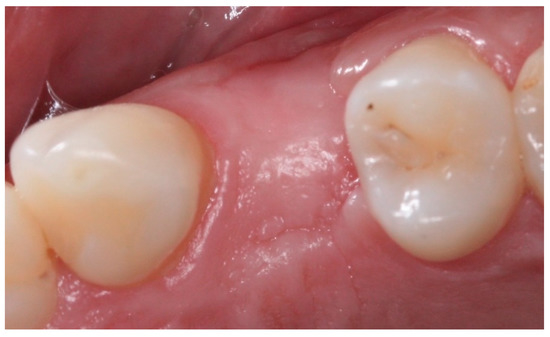

Socket Preservation Using a (Dense) PTFE Barrier with or without Xenograft Material: A Randomized Clinical Trial

2. Materials and Methods

2.4. Groups